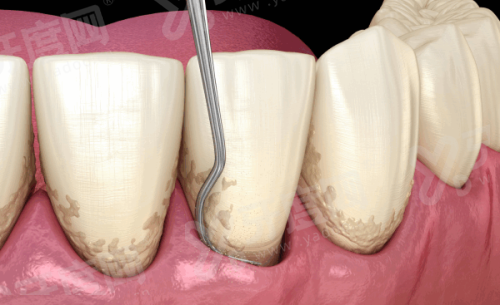

√ 种植牙的过程一般包括植入种植体、骨愈合、安装愈合基台、取模制作牙冠等步骤,整个过程需数月至半年不等,具体根据患者愈合情况而定。